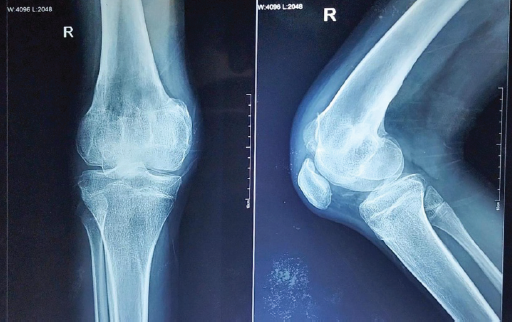

A 16-year-old male presented with complaints of deformity over his right knee for the past 2 years, associated with altered gait for the same period. He gives a history of a road traffic accident 2 years back, when he sustained a closed injury to his right knee. He was treated with indigenous splinting for 45 days, after which he was allowed to weight-bear and walk. On starting to weight bear, he noticed the deformity over his right knee. He was unable to extend his right knee fully, and his gait had changed following the injury. He was initially treated elsewhere with physiotherapy, but had no improvement in deformity, even though pain subsided. Even though he was managing functionally well with the deformity, he found it cosmetically displeasing to walk with the deformity. On examination, he had a short limb gait, a FFD of his right knee of around 30°, and multiple healed scars over his right knee were present. Bony thickening and broadening were felt over the distal femur. The range of right knee flexion was from 30° to 120°. A 3 cm femoral segment shortening was present on the right side. Distal neurovascular status was intact. Radiograph of right knee anteroposterior (AP) and lateral views (Fig. 1) were taken and showed a malunited fracture of the distal femur with open physis of the proximal tibia and fibula.

Figure 1 Presenting right knee radiograph

The distal femur physis was not clearly visible, suggesting that the injury was a distal femur physeal injury. Full-length radiographs of both lower limbs (Figs. 2) spanning from the hips to the ankles were taken to assess the mechanical axis of both lower limbs and to identify the pathology.